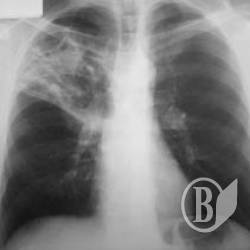

Захворюваність серед постраждалих у 2012р. становила 71,8 тис. випадків уперше встановлених діагнозів на кожні 100 тис. осіб, що перебували на обліку. Найбільш розповсюдженими були хвороби органів дихання (36,1 тис. випадків), системи кровообігу (5,6 тис.), шкіри і підшкірної клітковини (4,3 тис.), кістково-м’язової системи та сполучної тканини (4,0 тис.), сечостатевої системи (3,5 тис.) тощо.